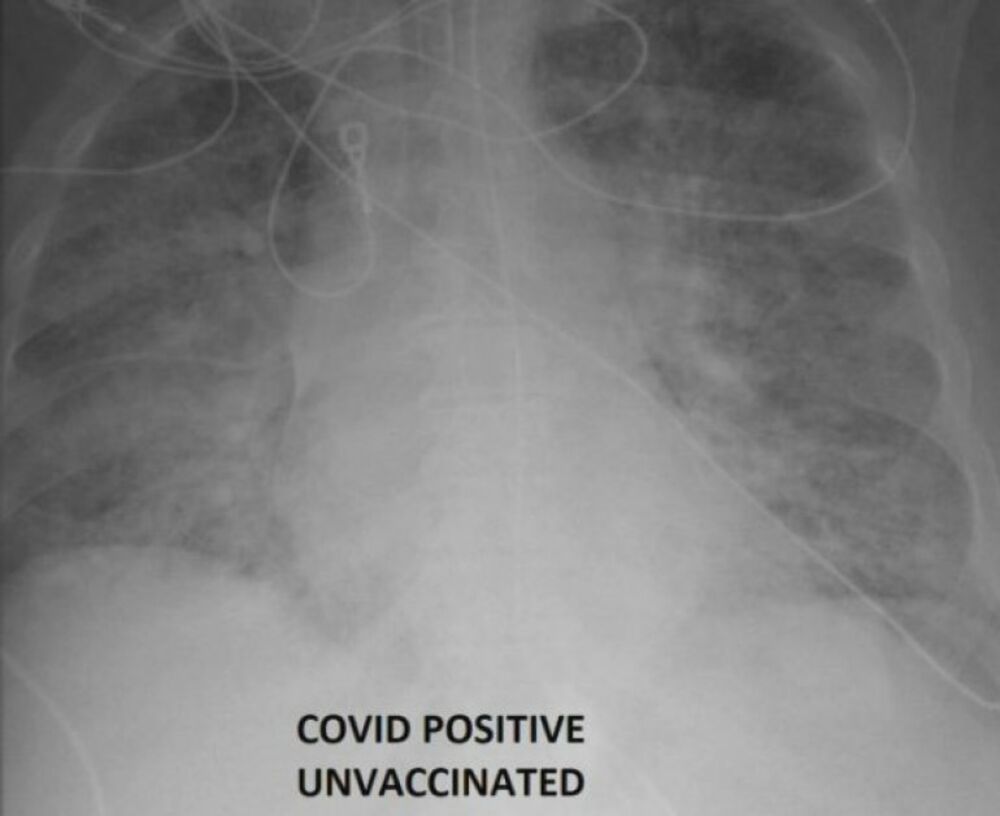

Ove snimke je objavio doktor, koji je prethodno lečio osobe zaražene kovidom, jednu vakcinisanu, drugu ne

Naime, ovi oštri rendgenski snimci otkrivaju razliku koju vakcine protiv kovida čine u odnosu na nezaštićena pluća kada ih napadne virus.

Ove snimke je objavio doktor, koji je prethodno lečio osobe zaražene kovidom, jednu vakcinisanu, drugu ne.

Rendgen nevakcinisane osobe pokazuje skoro potpuno bele organe - što znači da su ispunjeni virusom. Takođe imaju intenzivne ožiljke i čini se da im nedostaje vazduha koji ulazi u pluća.